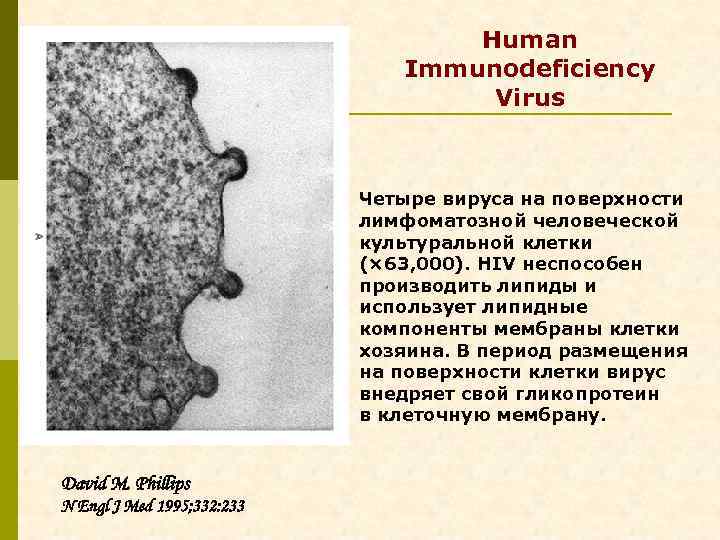

Human Immunodeficiency Virus Четыре вируса на поверхности лимфоматозной человеческой культуральной клетки (× 63, 000). HIV неспособен производить липиды и использует липидные компоненты мембраны клетки хозяина. В период размещения на поверхности клетки вирус внедряет свой гликопротеин в клеточную мембрану. David M. Phillips N Engl J Med 1995; 332: 233